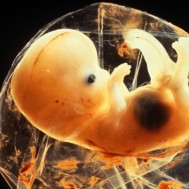

Baby: Week 6

You’re now making spontaneous movements, and can twitch your trunk and limb buds

Each day, changes make you more recognisable as a small person just like you. Now your lungs are forming![1] Brain function, as measured by EEG waves, can be recorded within days.[2] Nerve cells in the brain are connecting, forming primitive neural pathways. Your hands can bend at the wrist, and webbing is disappearing from your feet. Your tail is just about gone. Tastebuds are forming on your tongue.[3] You’re now making spontaneous movements, and can twitch your trunk and limb buds.[4]